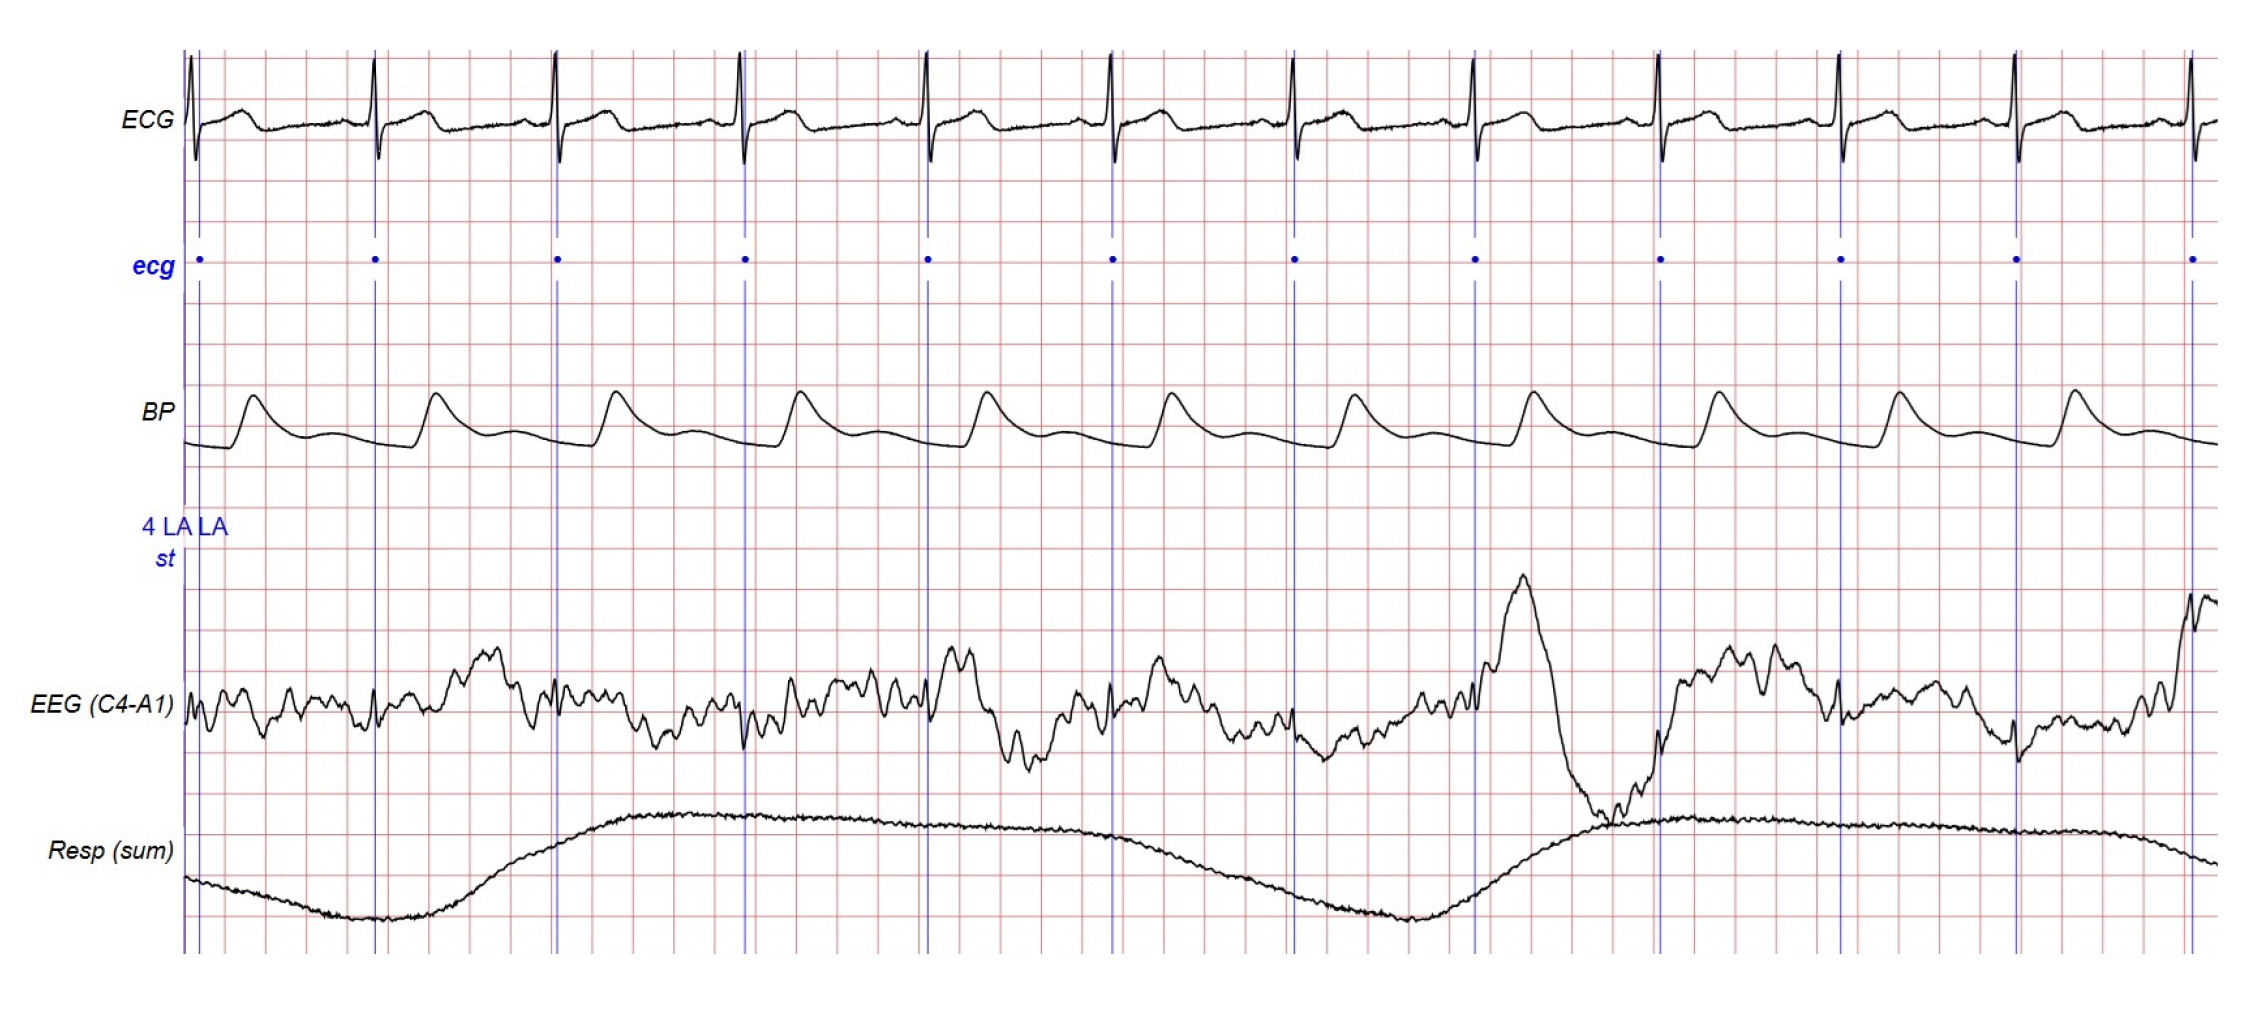

3. Dataset Used

4. Proposed Method

4.1. Time Domain: Halfwave Method